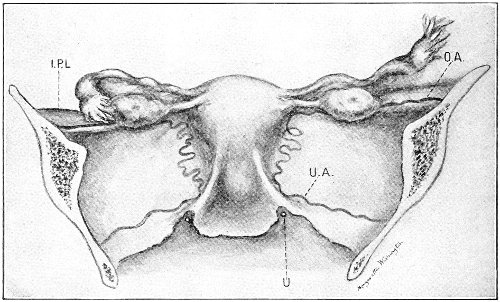

Vaginal and Bimanual Examination.—Having examined and noted the condition of the external genitals, the physician should next proceed to examine the vagina. The index finger of the right or the left hand should be gently introduced into the vagina. The condition of the vaginal walls, and the direction, consistency, form, etc. of the vaginal cervix, may be determined. The shape and size of the os uteri should be noted. The ulnar edge and the tips of the fingers of the other hand should then be placed upon the abdomen, immediately above the symphysis pubis, and gently pressed backward and downward toward the vaginal finger 24 (Fig. 2). In this way the various pelvic organs, the uterus, Fallopian tubes, ovaries, and ureters, may be palpated between the two hands, and their position, size, shape, and consistency may be determined. Such an examination is, of course, made much more easily in a thin woman than in a fat one. A thin woman a few weeks after labor may be examined most easily, on account of the relaxation of the abdominal and vaginal walls.

In making the bimanual examination the structures 25 should be palpated methodically in order. The vaginal finger notes the condition of the cervix uteri. If the fundus be in the normal position, the uterus can then be taken between the abdominal hand (upon the fundus) and the vaginal finger (upon the cervix) (Fig. 3). The shape, size, mobility, and consistency are noted. The vaginal finger is then passed anteriorly and laterally toward either uterine cornu, while the abdominal fingers pass over to the posterior aspect of the same cornu. The ovarian ligament and the proximal end of the Fallopian tube may thus be felt. Passing farther outward, the whole of the tube and the ovary may be examined. The same procedure is then applied to the opposite side.